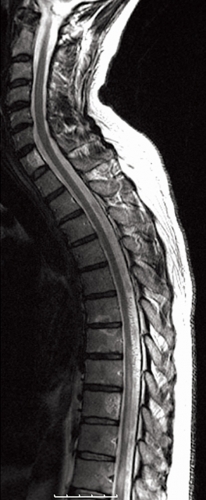

Ånyo gjordes en akut MRT inklusive spinal kontrastförstärkt MR-angiografi som påvisade en spinal dural arteriovenös fistel i nivå med Th11. En diagnostisk konventionell spinal angiografi verifierade diagnosen, och i samma seans kunde fisteln behandlas endovaskulärt utan komplikationer (Figur 2). Patienten överfördes till vårdavdelning, där man redan några dagar efter behandlingen noterade en påtaglig regress av samtliga symtom: han klarade då att stå och gå – dock med gåbord. Vid klinisk kontroll efter sex månader kunde patienten gå obehindrat och uppvisade nästan fullständig regress av övriga symtom. Han hade även bibehållen erektionsförmåga.

Undersökningen visade vidgade perimedullära kärl och ryggmärgsödem, fynd typiska för en spinal dural arteriovenös fistel med sekundär myelopati (Figur 3). På vårdavdelning i väntan på spinal angiografi och embolisering av fisteln försämrades patienten ytterligare och blev avföringsinkontinent. Akut spinal angiografi verifierade diagnosen, och man gjorde ett emboliseringsförsök som fick avbrytas på grund av svårigheter att nå bra kateterläge (Figur 4). Fisteln kunde slutas kirurgiskt senare samma dag.

Diagnostik. Den kliniska bilden och spinal MRT är helt avgörande för diagnosen. Okunnighet hos kliniker eller radiolog kan få som konsekvens att diagnosen ställs för sent eller inte alls, medan patienten utvecklar en obotlig parapares. De typiska fynden vid MRT är ödem och lätt svullnad av ryggmärgen torakolumbalt samt vidgade blodkärl (vener) dorsalt perimedullärt. Ödemet uppvisar hög signal centralt i ryggmärgen på T2-viktade bilder. De vida perimedullära venerna syns i cerebrospinalvätskan som slingriga strukturer med låg signal på T2-viktade bilder och hög signal på T1-viktade bilder efter intravenös kontrastmedelstillförsel.

Ibland ses även kontrastmedelsuppladdande områden intramedullärt; subtila direkt efter kontrastinfusion och alltmer framträdande efter 40–45 minuter [7]. På kontrastförstärkt MR-angiografi framträder de stasade venerna som stora slingriga kärlstrukturer; en viktigare funktion med denna undersökning är dock att identifiera nivån för fisteln genom att påvisa den dilaterade radikulomedullära ven i vilken fisteln tömmer sig. Detta medför en mycket stor fördel vid genomförandet av den konventionella spinala angiografin, speciellt hos äldre patienter med omfattande arterioskleros och slingriga kärl [4, 8].